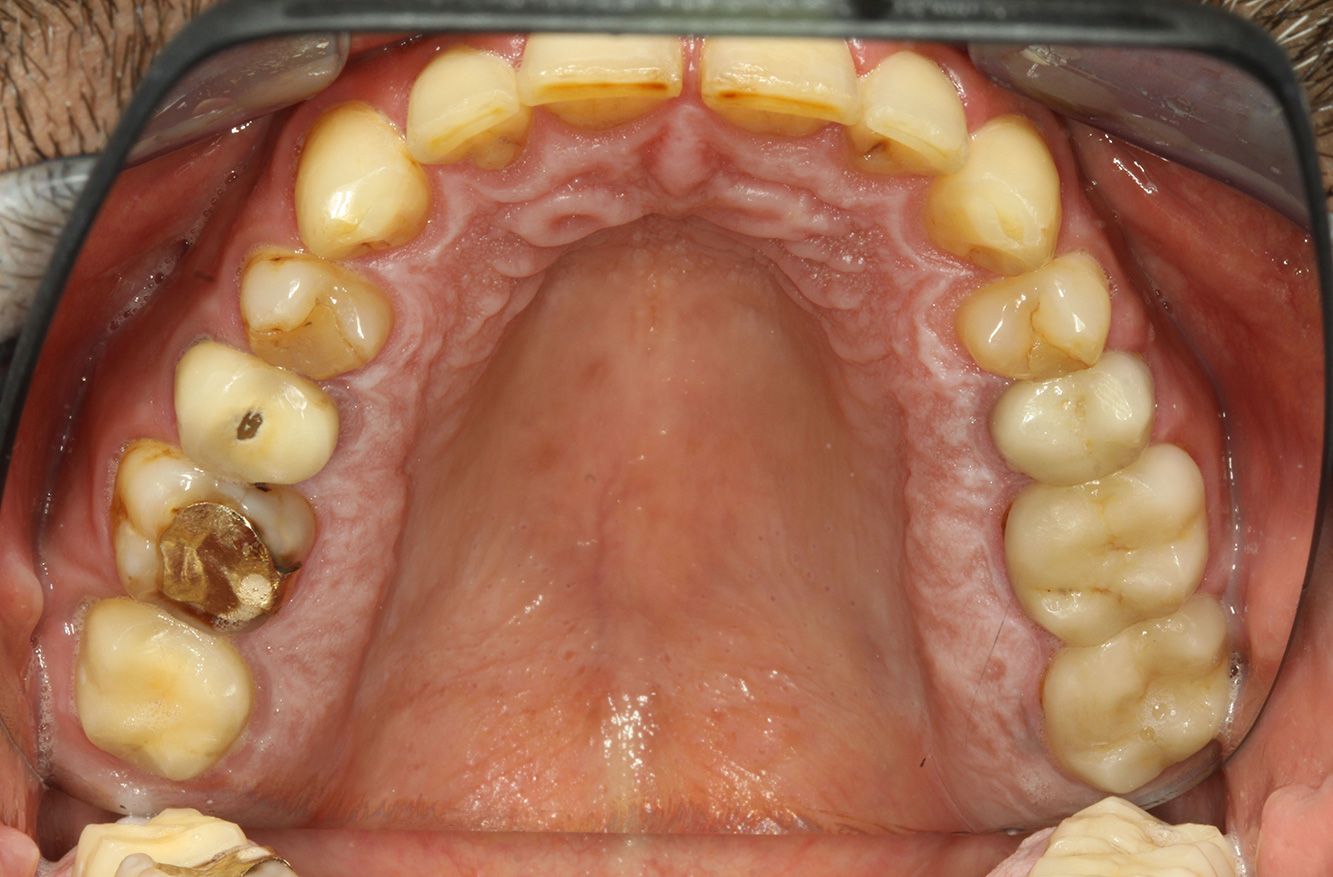

Der Endokarditis-Patient mit aktiven Kariesläsionen*

Der Patient ist 39 Jahre mit Z.n. Herzklappenersatz wegen Klappenfehlers und Endokarditis. Als Antikoagulans (Gerinnungshemmer) wird regelmäßig ASS 100 eingenommen. Aus dem Bereich Lebensstil ist die Ernährungsweise als kariesfördernd einzustufen, da mit hoher Regelmäßigkeit zuckerhaltige Lebensmittel sowie sechs bis sieben Mahlzeiten täglich verzehrt werden. Die Mundgesundheit des Patienten zeigt ein mittleres Kariesrisiko mit aktiven Läsionen. Das Parodontitisrisiko ist niedrig, es besteht eine Gingivitis. Es ergeben sich folgende Empfehlungen für die Prophylaxebehandlung.

Für die Prophylaxesitzung lassen sich keine spezifischen Instrumentierungsempfehlungen ableiten. Durch den gezielten Einsatz von Pulverstrahl und rotierend Polieren können Plaque und Verfärbungen an den Restaurationsrändern schonend entfernt und Wiederbesiedlungsnischen für kariogene Bakterien reduziert werden (20).